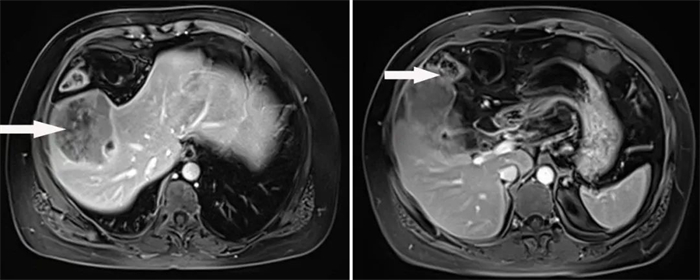

患者3,55歲女性,因“上腹部疼痛1周”入院,經(jīng)MRI檢查提示肝內(nèi)占位性病變,累及膽囊、橫結(jié)腸,考慮肝惡性腫瘤。